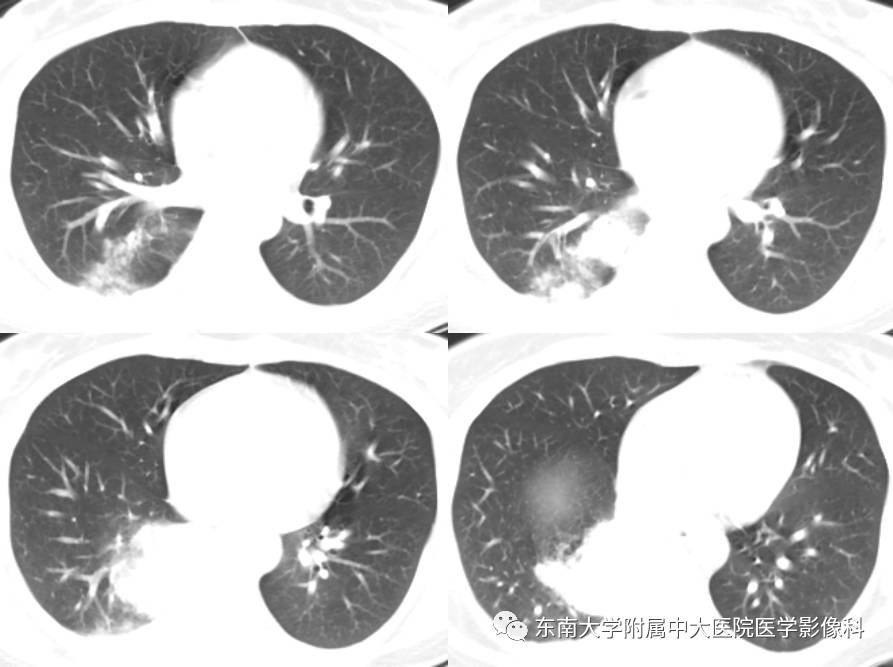

【病例】肺隔离症1例CT影像表现

女,38岁,因“间断咯血2月余”入院。